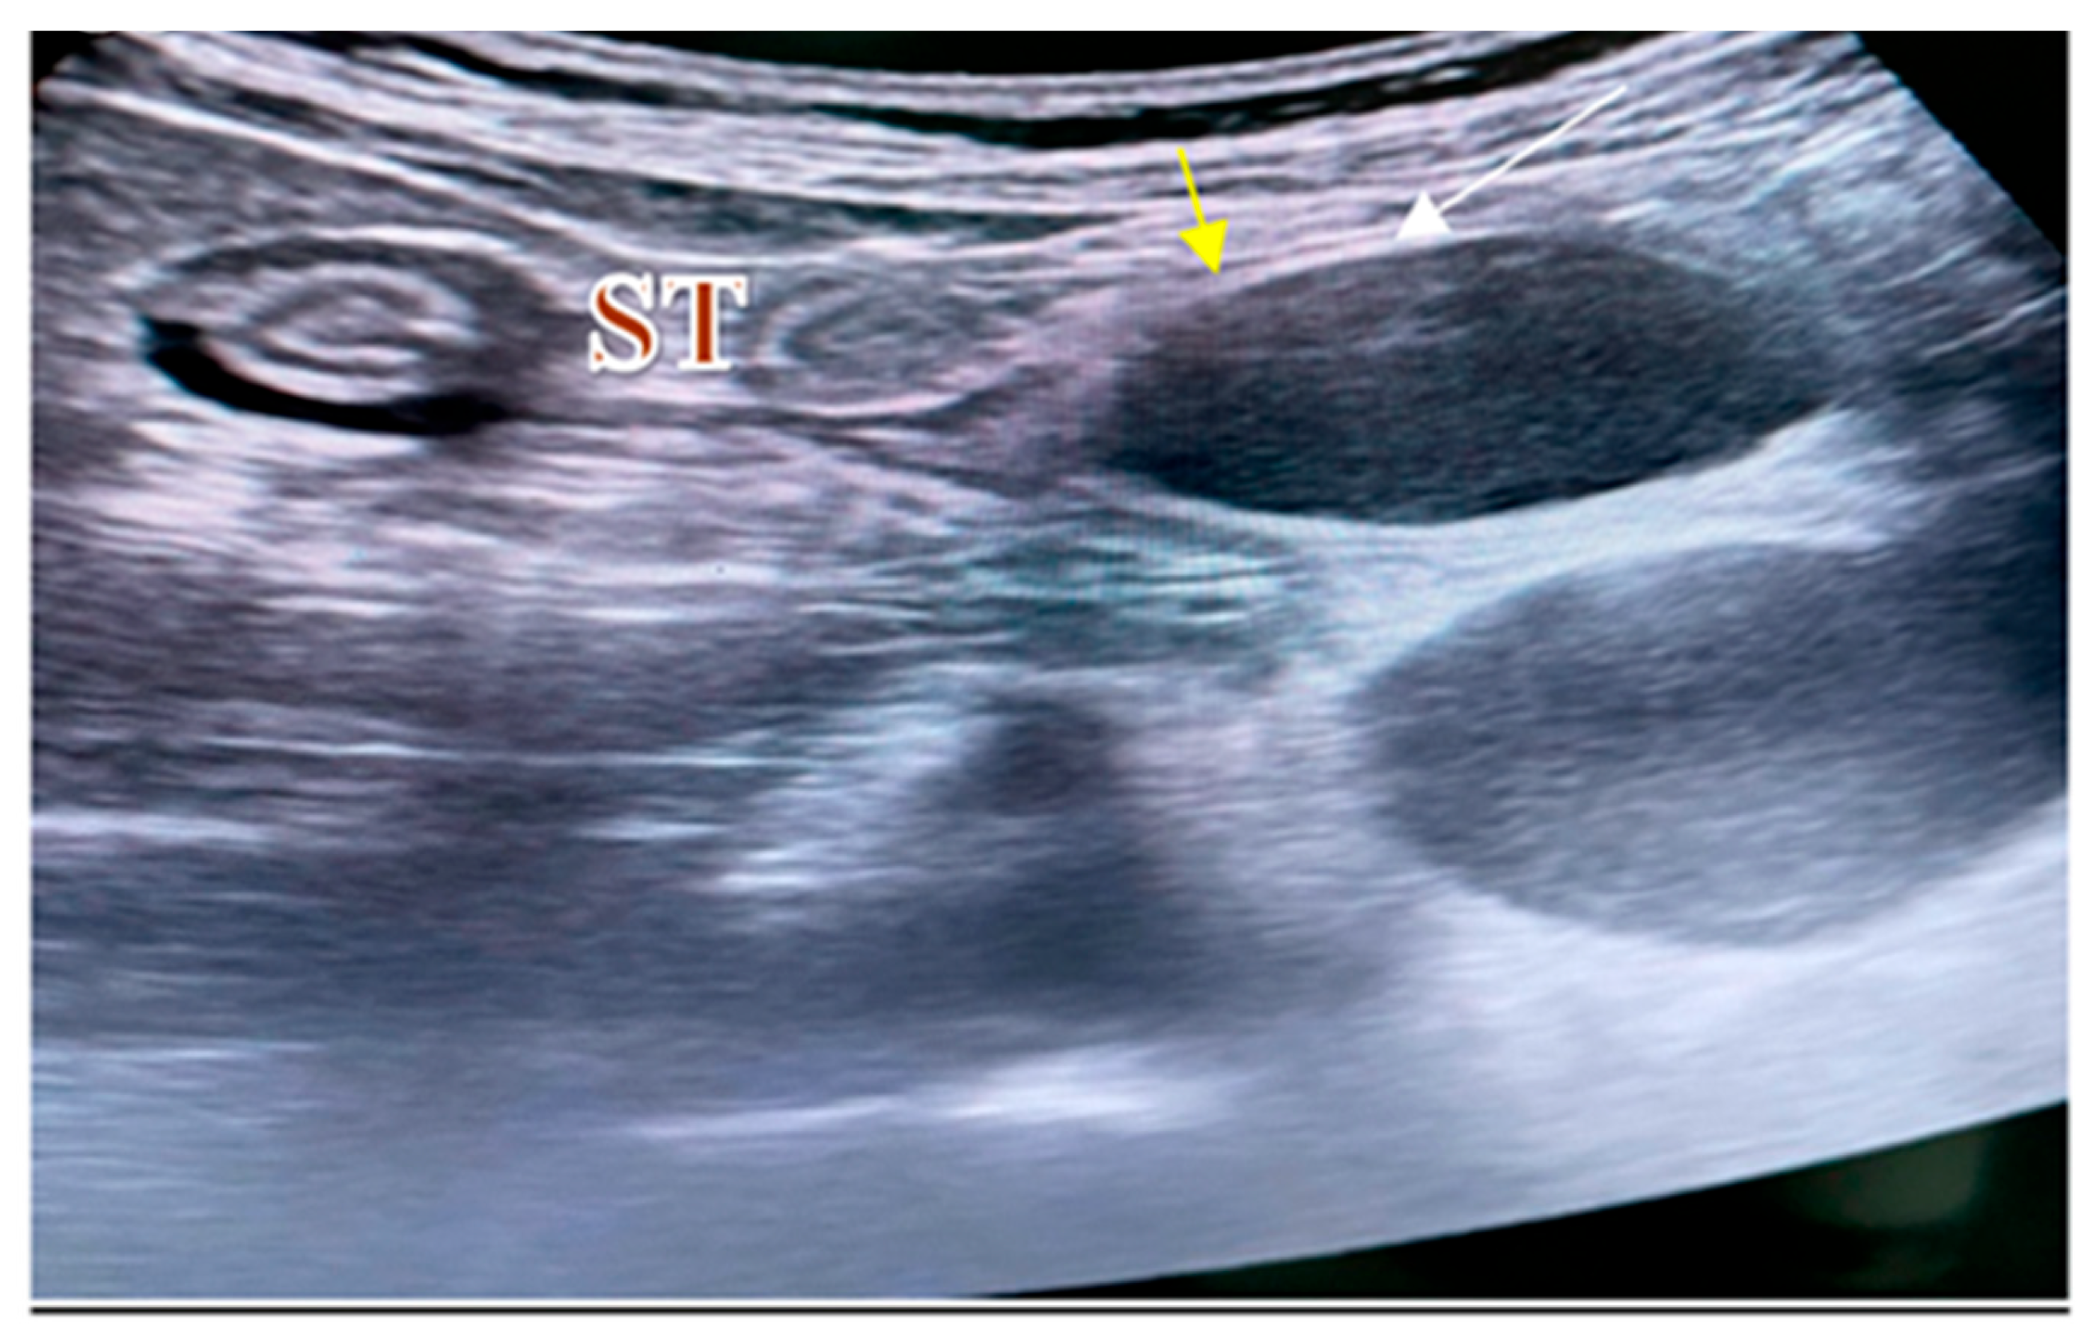

2. Case Report